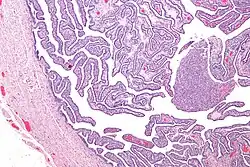

Micrograph of salpingitis – a component of pelvic inflammatory disease. H&E stain.

Upon a pelvic examination, cervical motion, uterine, or adnexal tenderness will be experienced.[5] Mucopurulent cervicitis and or urethritis may be observed. In severe cases, more testing may be required, such as laparoscopy, intra-abdominal bacteria sampling and culturing, or tissue biopsy.[15][23]